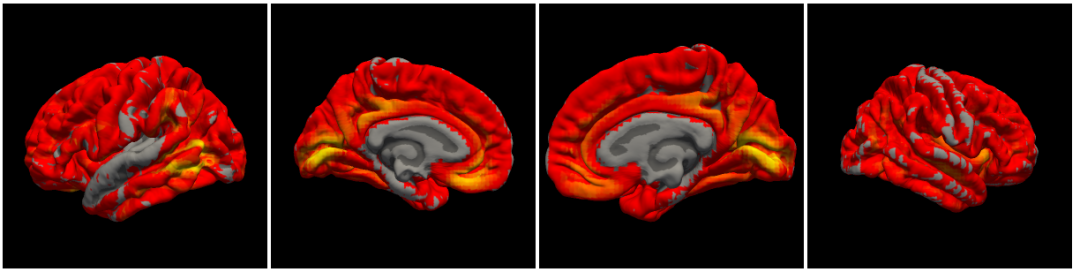

变换后的DK模板map到mni152_T1

由于做了resample所以分辨率在mni152上看有所下降